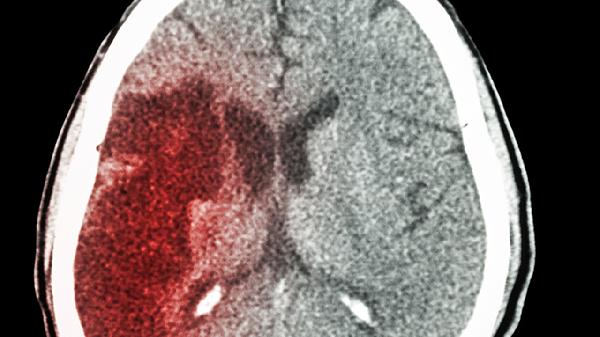

车祸、坠落等外力撞击头部可引发创伤性脑出血,常见硬膜外血肿或脑挫裂伤。伤后可能出现意识障碍进行性加重,CT显示高密度出血灶。需根据血肿量选择保守观察或开颅血肿清除术,恢复期需进行肢体功能康复训练。